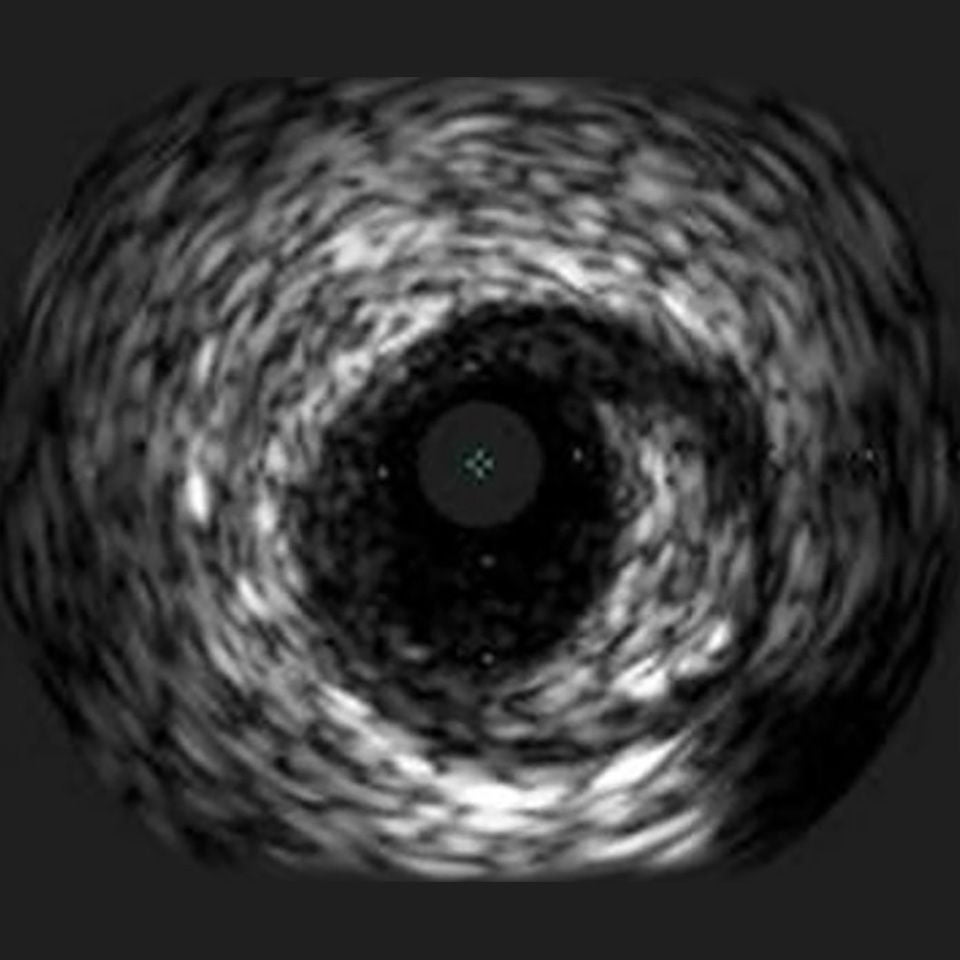

OPTICROSS HD Imaging Catheter 60MHz

IVUS image of inside a coronary vessel using the 60MHz Opticross catheter

Axial resolution: 22µm

High-Definition IVUS image quality helps physicians more accurately identify lesion length, assess plaque morphology, and determine the tools required for vessel prep. See how OPTICROSS HD’s 60 MHz images stack up against the competition.